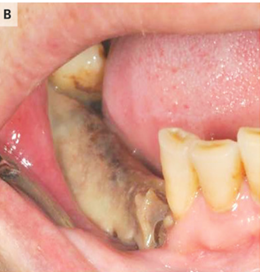

口腔内を観察すると、下顎骨が露出していた。

最終診断としては口腔外瘻孔形成を伴う二次感染を合併した薬剤関連顎骨壊死と診断した。